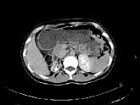

女,35岁,右侧腰部不适,CT增强扫描如图所示,下列说法正确的是()

A.右肾轮廓明显小于左侧,边缘光滑规则

B.左肾代偿性肥大

C.考虑为右小肾畸形

D.右肾完全无功能

E.考虑为右肾肾自截

女,35岁,右侧腰部不适,CT增强扫描如图所示,下列说法正确的是()<img border="0" style="width: 171px; height: 128

[多选题]女,35岁,右侧腰部不适,CT增强扫描如图所示,下列说法正确的是()A.右肾轮廓明显小于左侧,边缘光滑规则B.左肾代偿性肥大C.考虑为右小肾畸形D.右

[多选题]女,35岁,右侧腰部不适,CT增强扫描如图所示,下列说法正确的是()A.右肾轮廓明显小于左侧,边缘光滑规则B.左肾代偿性肥大C.考虑为右小肾畸形D.右